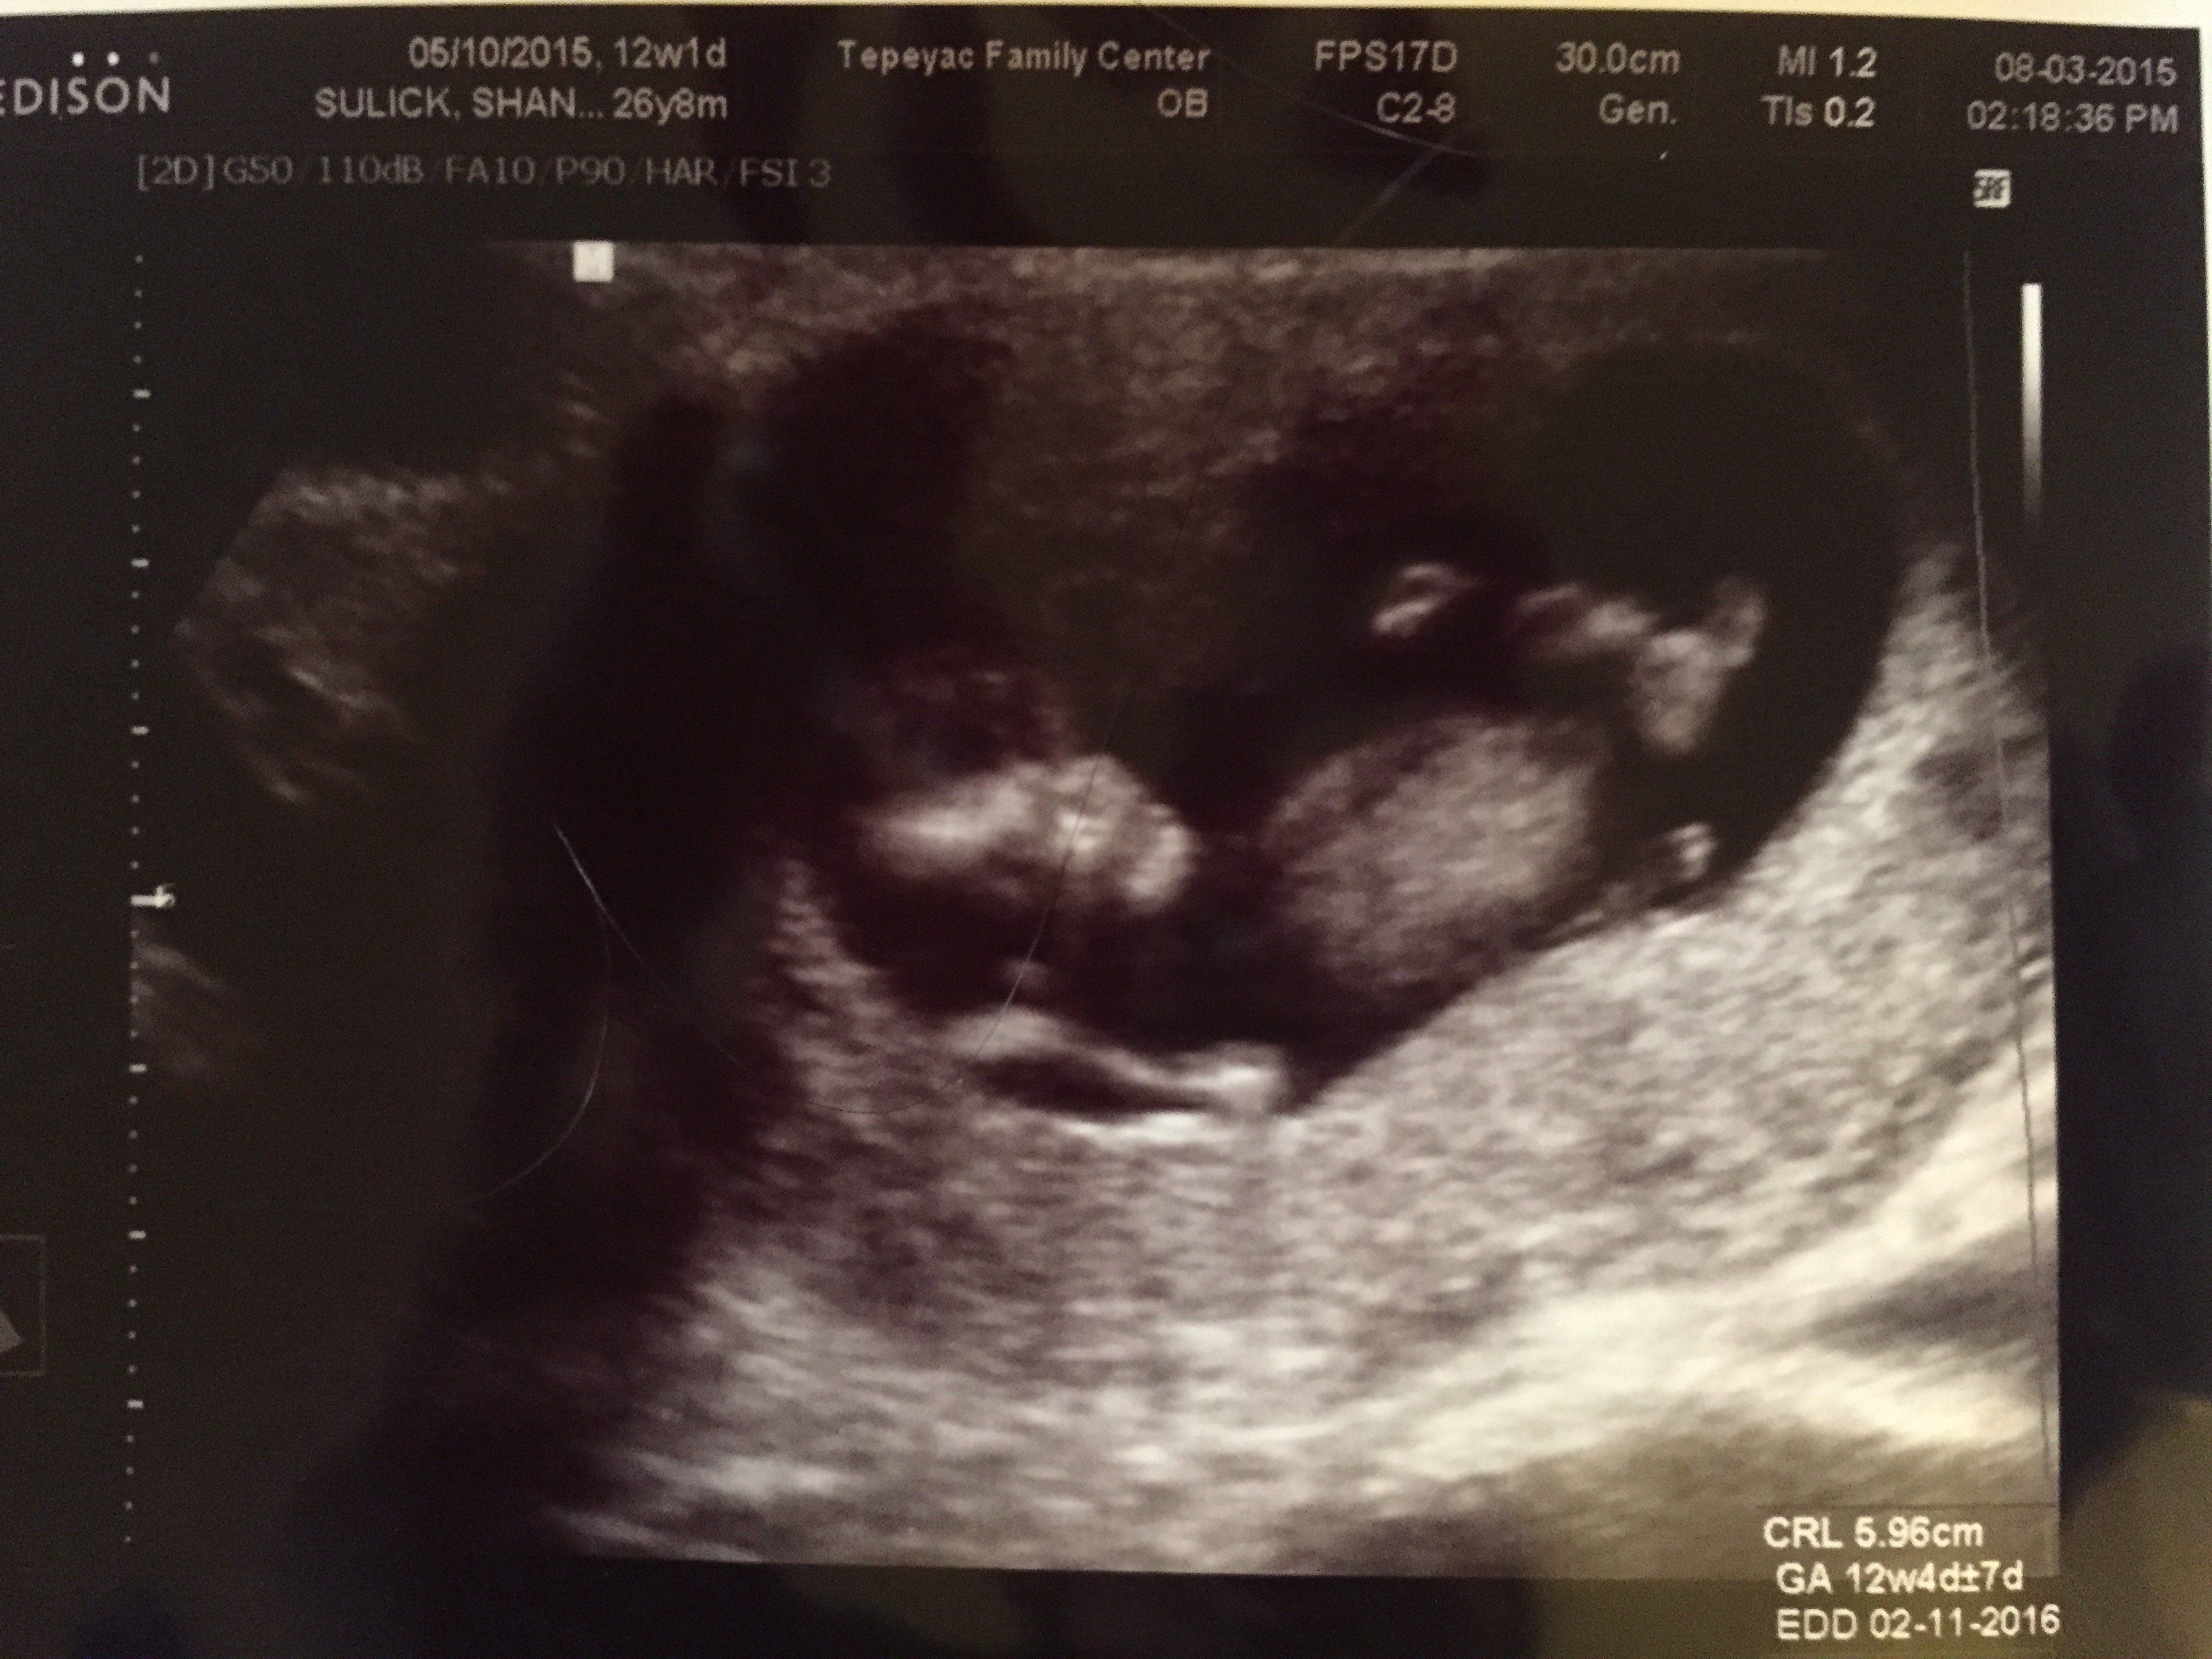

Andrew and I went for our second sonogram when I was twelve weeks along.  We were both delighted and amazed as we watched our little son or daughter jumping around my uterus, lifting little arms, kicking little legs.  As the technician commented about our child’s energy levels, I laughed, and we watched in amazement as our baby jumped on the screen in response.  To this day, it remains one of the most memorable events of my entire pregnancy.

IMG_0523At twelve weeks, we were preparing to make our wonderful news public.  I had written a blog post about our baby; I had ordered postcards that showed a happily married couple on their honeymoon in Disney and announced that it had also been our first family vacation.  Everyone was thrilled to hear our news.  We were congratulated constantly, and Andrew and I were thrilled to finally be able to share our secret.